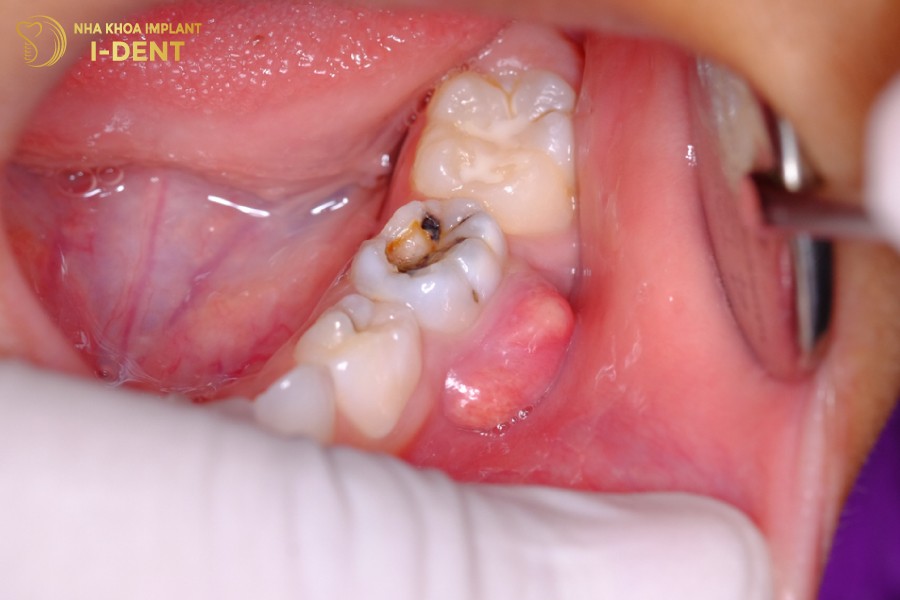

Thối tủy răng là tình trạng do viêm nhiễm tủy răng nghiêm trọng, gây biến đổi màu răng và tạo ra mùi hôi khó chịu trong khoang miệng, tăng nguy cơ răng lung lay, nứt gãy, mất răng. Nếu không được xử lý kịp thời sẽ dẫn đến tình trạng áp xe chân răng, rỉ dịch mủ, nghiêm trọng hơn là bị nhiễm trùng máu.

- Răng bị hư tủy thường có vết sâu lớn hoặc bị vỡ mẻ.

Sâu răng tạo nên những lỗ sâu làm mòn ngà răng, tạo cơ hội cho vi khuẩn tấn công và xâm nhập vào sâu bên trong tủy răng, gây hư, thối.